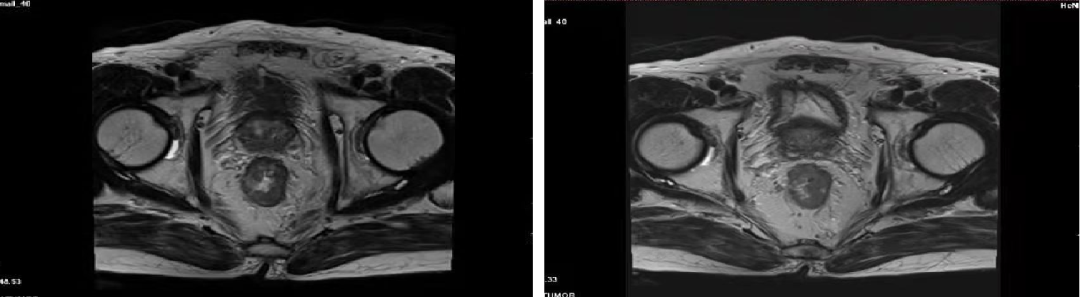

02 初诊病史

诊断:直肠腺癌双肺转移IV期,KRAS 突变型,MSS。高龄,患者及家属无手术意愿,全身系统治疗。